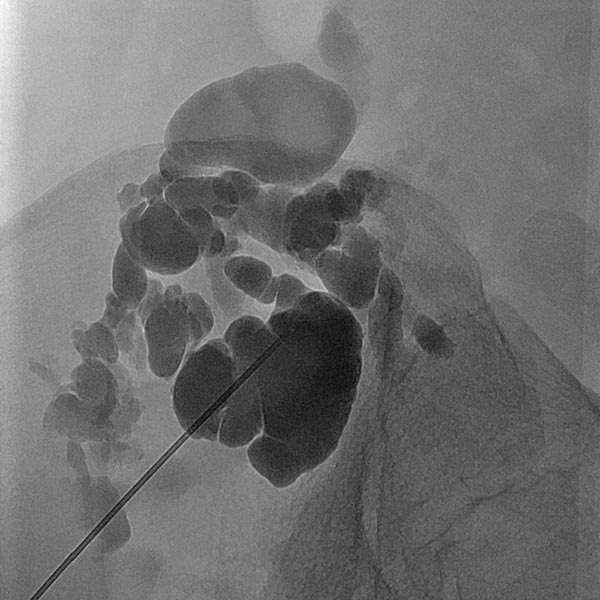

Overview X-ray in the area of the right pelvic crest after injection of contrast medium via the needle directly located in the lymphatic malformation. Large parts of the lymphatic malformation are contrasted from this needle position, representing an optimal needle position for sclerotherapy.